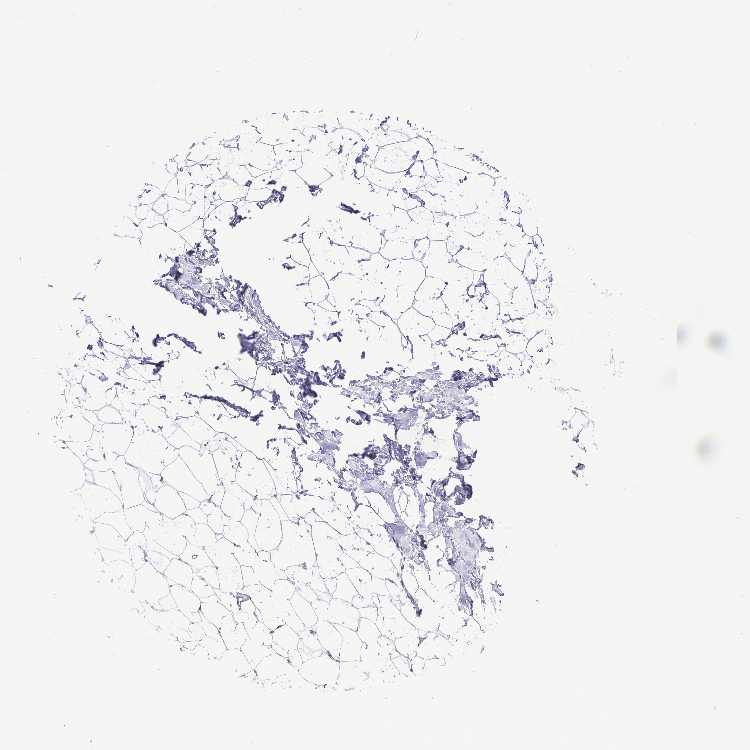

BREAST - Antibody stainingi

Antibody staining in the annotated cell types in the current human tissue is reported as not detected, low, medium, or high, based on conventional immunohistochemistry profiling in selected tissues. This score is based on the combination of the staining intensity and fraction of stained cells.

Each image is clickable and will lead to virtual microscopy that enables deeper exploration of all samples and also displays staining intensity scores, fraction scores and subcellular localization as well as patient and tissue information for each sample.

Antibody HPA062724Antibody HPA063392

Adipocytes Not detectedNot detected

Glandular cells Not detectedLow

Myoepithelial cells MediumNot detected